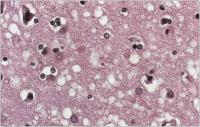

Spongiforme Enzephalopathie

Abbildung 1: Typische spongiforme Gewebealteration in der Großhirnrinde bei CJK (Hämatoxylin-Eosin-Fbg.)

Keywords: Cortex cerebriGroßhirnrindeHistologisches PräparatNeurologieSpongiforme Enzephalopathie